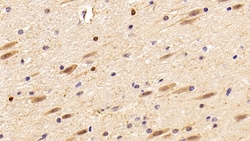

IBA1 Polyclonal Antibody for Western Blot, IHC (P)

Ionized calcium-binding adapter molecule 1 (IBA1), also known by its gene name AIF1, is a protein expressed predominantly by microglia in the brain and spinal cord. This protein belongs to the EF-hand calcium-binding protein family and plays a crucial role in microglial activation and migration in response to brain injury or neuroinflammation. IBA1's function is integral to microglial motility and phagocytic activity, facilitating the cellular response to pathogenic stimuli and promoting tissue homeostasis and repair in the central nervous system. IBA1 serves as a reliable marker for activated microglia in various neurological disorders, including Alzheimer's disease, Parkinson's disease, and multiple sclerosis, where increased expression correlates with disease progression and severity. The protein's structural features enable it to bind calcium ions, inducing conformational changes that activate signaling pathways essential for microglial function. Its expression is highly regulated by inflammatory cytokines, underpinning its role in neuroimmune responses. Due to its specific expression in microglia during pathological conditions, IBA1 is widely used in research as a marker to study microglial status and activity, and it remains a focal point for understanding microglial involvement in neurodegenerative diseases.Specifications

| Immunohistochemistry (Paraffin), Western Blot | |